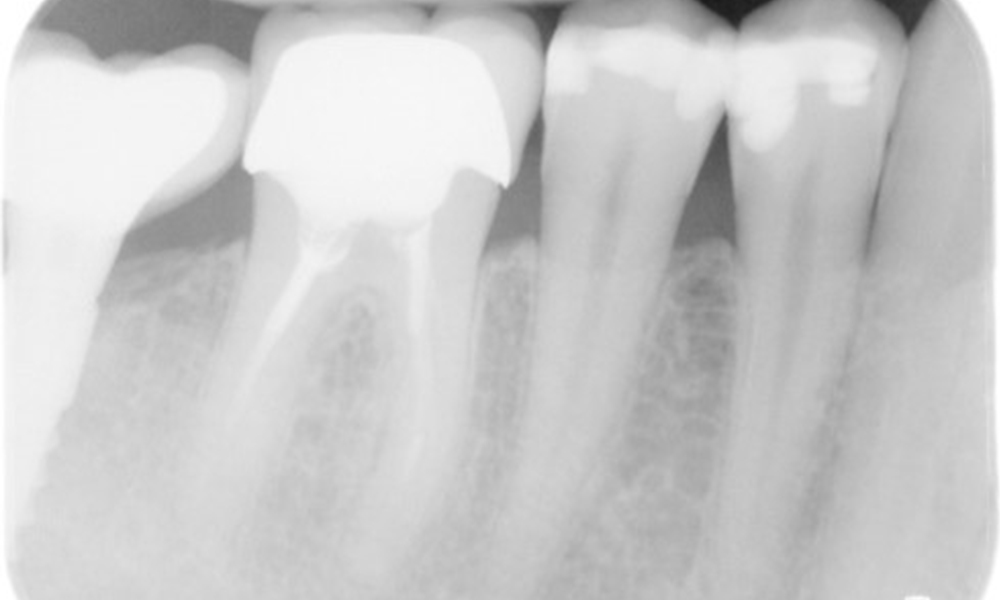

Der Patient hat einige zahnärztliche Restaurationen und zwei Implantate (2. und 4. Quadrant). Anhand der aktuellen Befunde lässt sich eine Gingivitis bei stabilem parodontalen Zustand am reduzierten Parodont (Stadium III, Grad A) feststellen.

Der Patient zeigt keine besonderen Risikofaktoren mit spezifischen zahnmedizinischen Auswirkungen. Daher ist der aus der Mundgesundheit ermittelte Bedarf maßgebend. Hierbei zeigt sich eine gute Mundgesundheit mit stabilem, reduzierten Parodont. Sollte sich bei einem Kontrolltermin am Implantat eine Vergrößerung von ST im Vergleich zur Baseline kombiniert mit einer diffusen Blutung zeigen, so sollte eine Röntgendiagnostik (i. S. eines Zahnfilms) erfolgen, um frühzeitig einen periimplantären Knochenverlust zu erkennen und dagegen zu intervenieren.